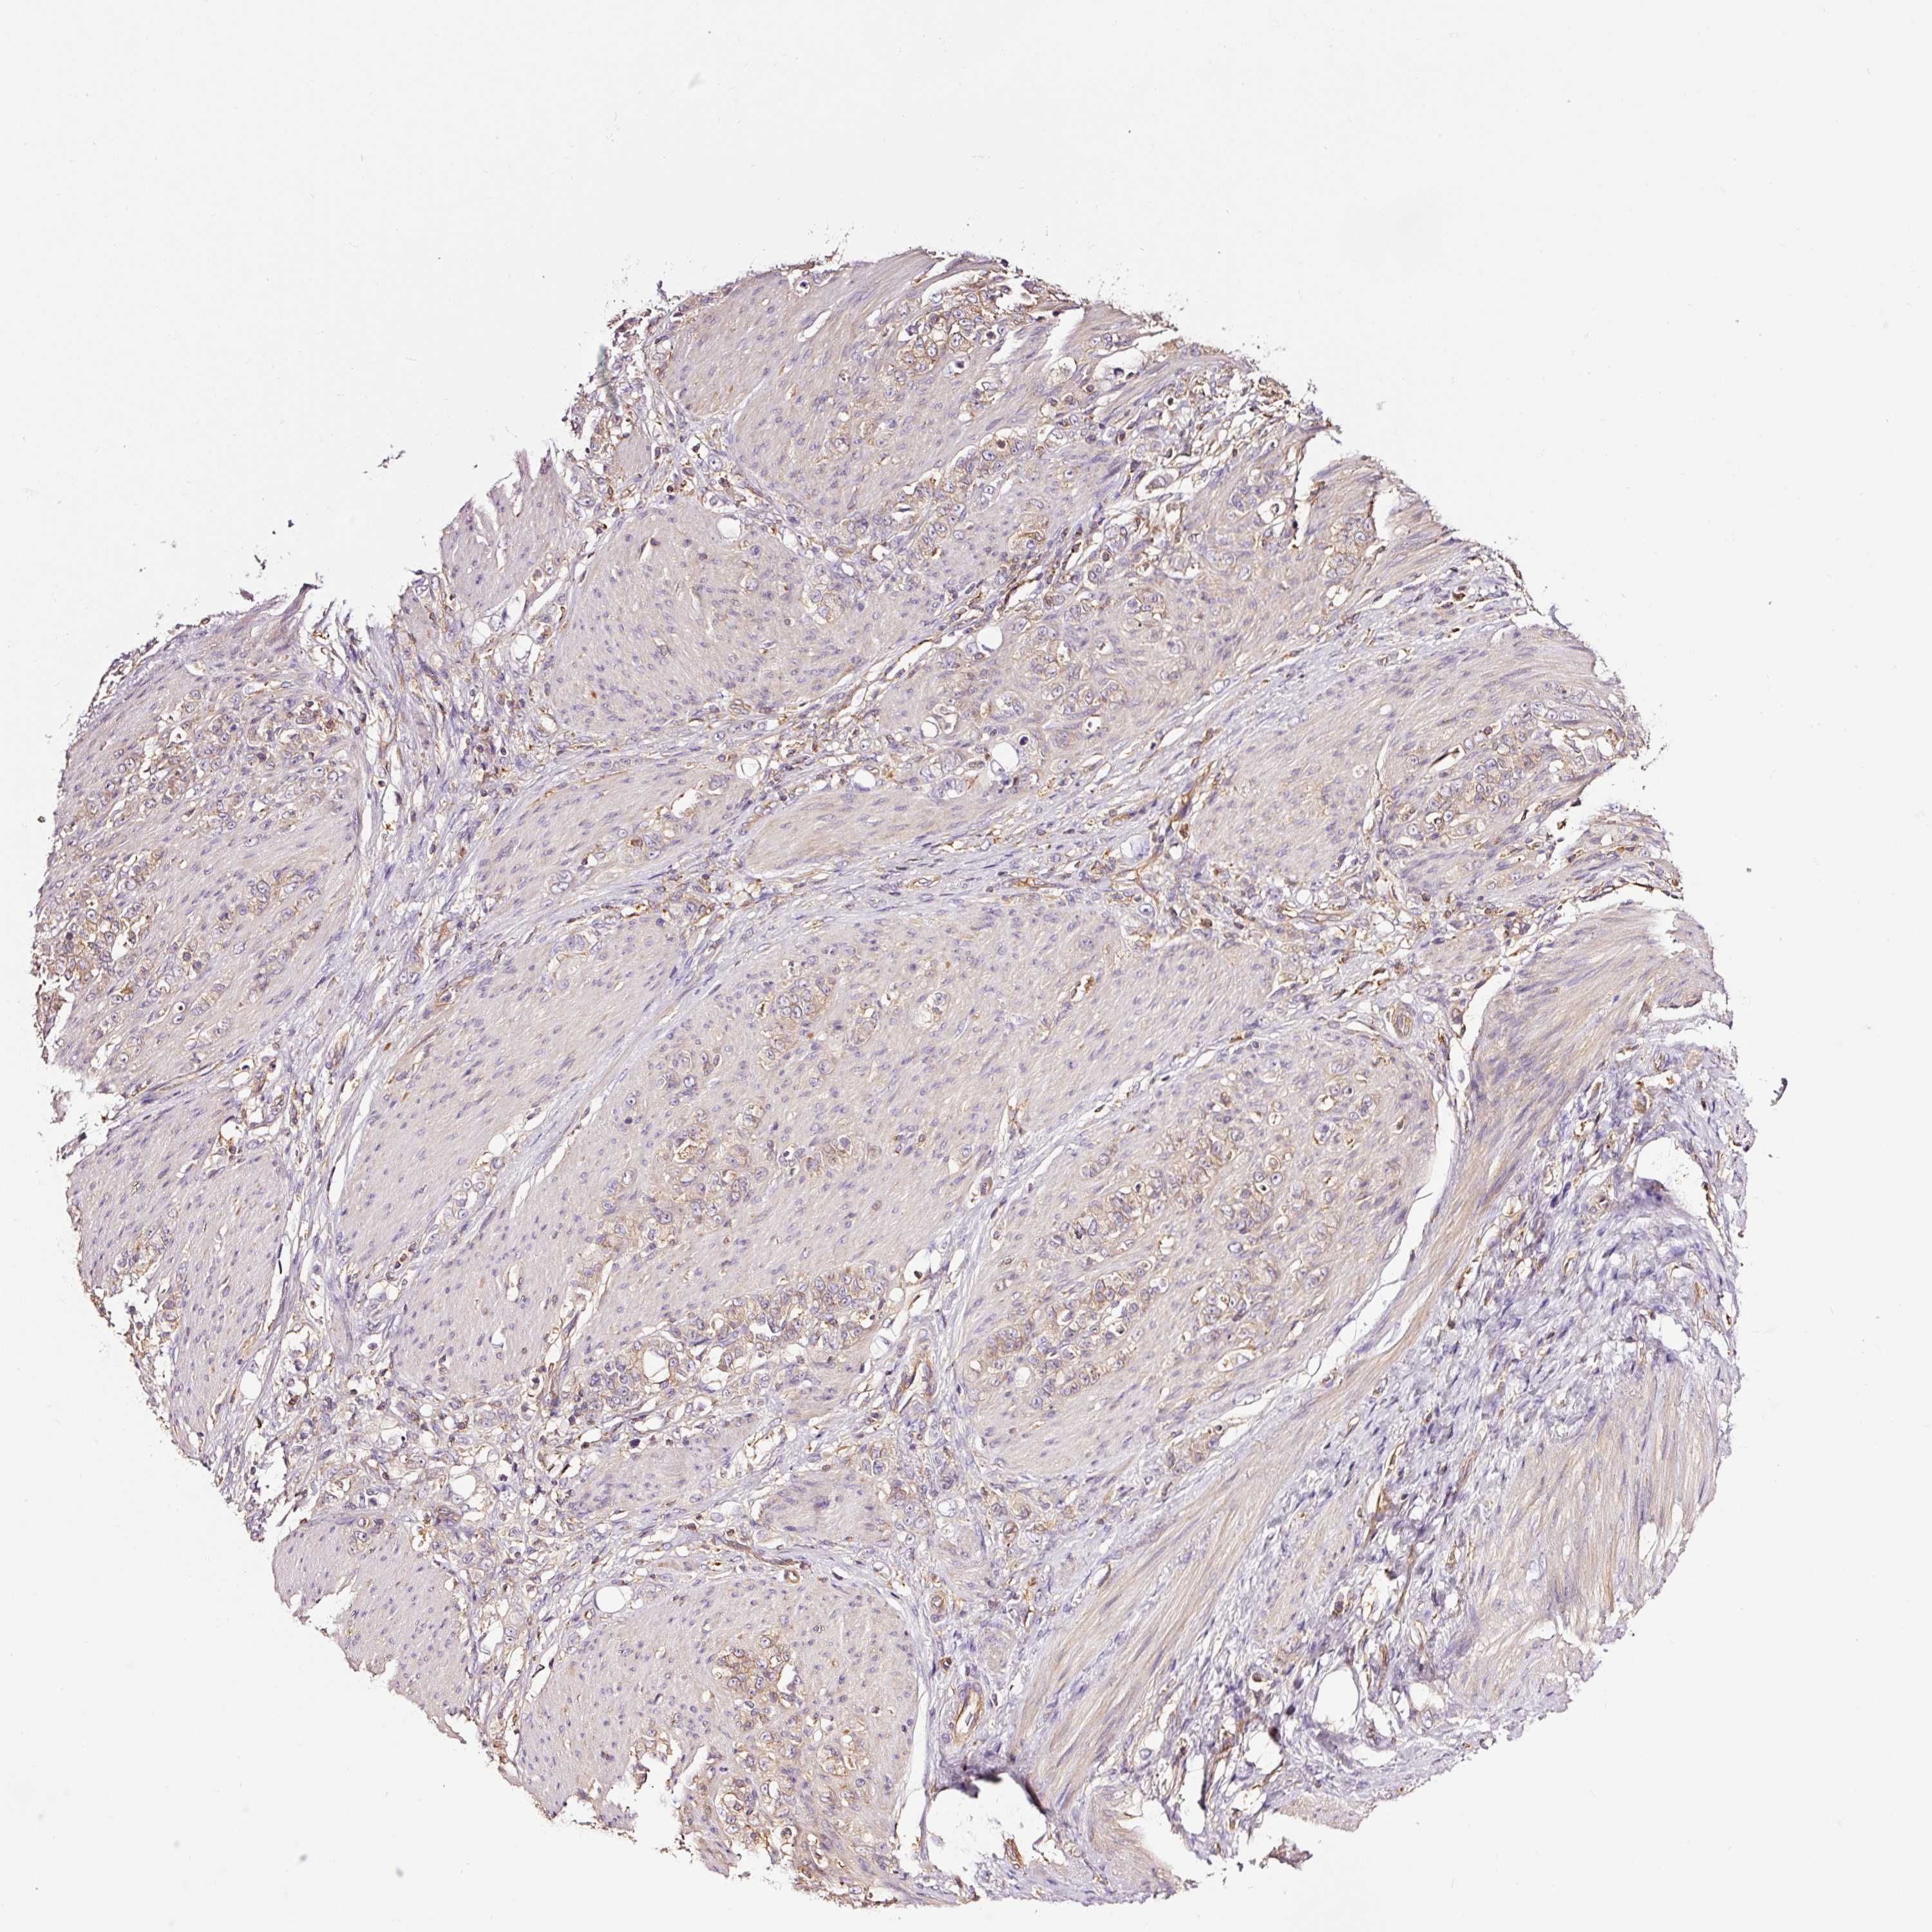

STOMACH CANCER - Protein expressioni

A mouse-over function shows sample information and annotation data. Click on an image to view it in a full screen mode. Samples can be filtered based on level of antibody staining by selecting one or several of the following categories: high, medium, low and not detected. The assay and annotation is described here.

Note that samples used for immunohistochemistry by the Human Protein Atlas do not correspond to samples in the TCGA dataset.

Antibody stainingi

Antibody staining in the annotated cell types in the current human tissue is reported as not detected, low, medium, or high, based on conventional immunohistochemistry profiling in selected tissues. This score is based on the combination of the staining intensity and fraction of stained cells.

Each image is clickable and will lead to virtual microscopy that enables deeper exploration of all samples and also displays staining intensity scores, fraction scores and subcellular localization as well as patient and tissue information for each sample.

Antibody HPA037997

Antibody HPA037998

Antibody CAB025485

Staining

Adenocarcinoma, NOS